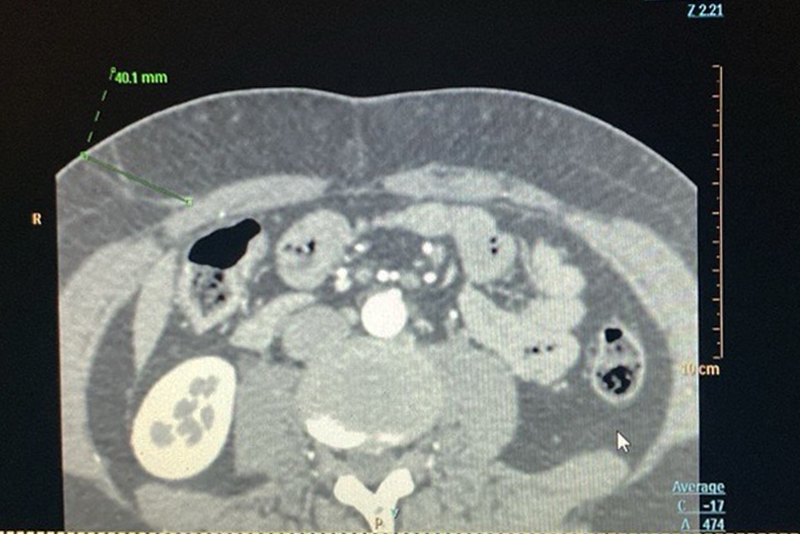

Es un conjunto de técnicas de última generación que permiten procesar y analizar imágenes médicas con precisión milimétrica. Estas herramientas son fundamentales para planificar intervenciones complejas, medir volúmenes exactos o trazar mapas vasculares detallados, especialmente en contextos quirúrgicos.

Se utiliza en cirugías oncológicas, procedimientos reconstructivos, planificación de radioterapia y en la evaluación de enfermedades complejas como patologías neurodegenerativas o hepáticas.

Estos estudios requieren imágenes de alta calidad obtenidas mediante resonancia magnética o tomografía computarizada, en algunos casos con medio de contraste.